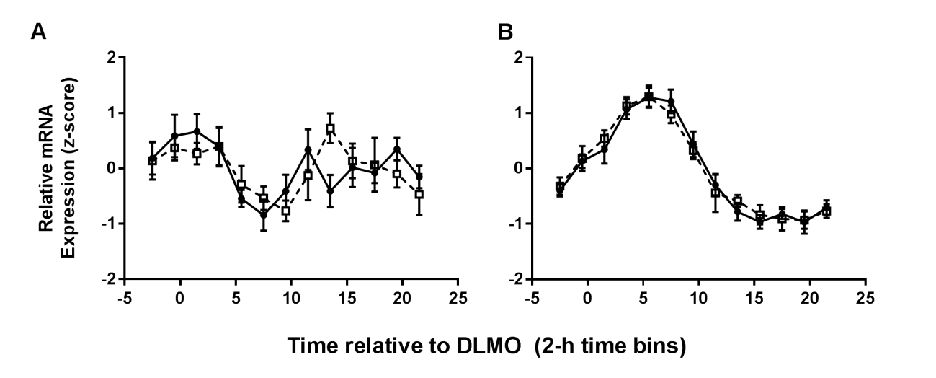

Clock gene expression patterns in adipose tissue are compared between the two meal timing conditions, revealing tissue-specific circadian phase shifts.

Meal Timing Regulates the Human Circadian System.

Per2 and other clock gene transcript levels measured from peripheral blood samples demonstrate delayed phase alignment consistent with the shifted meal schedule.

Meal Timing Regulates the Human Circadian System.